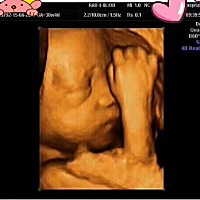

卸货啦!胖小子8.3哦